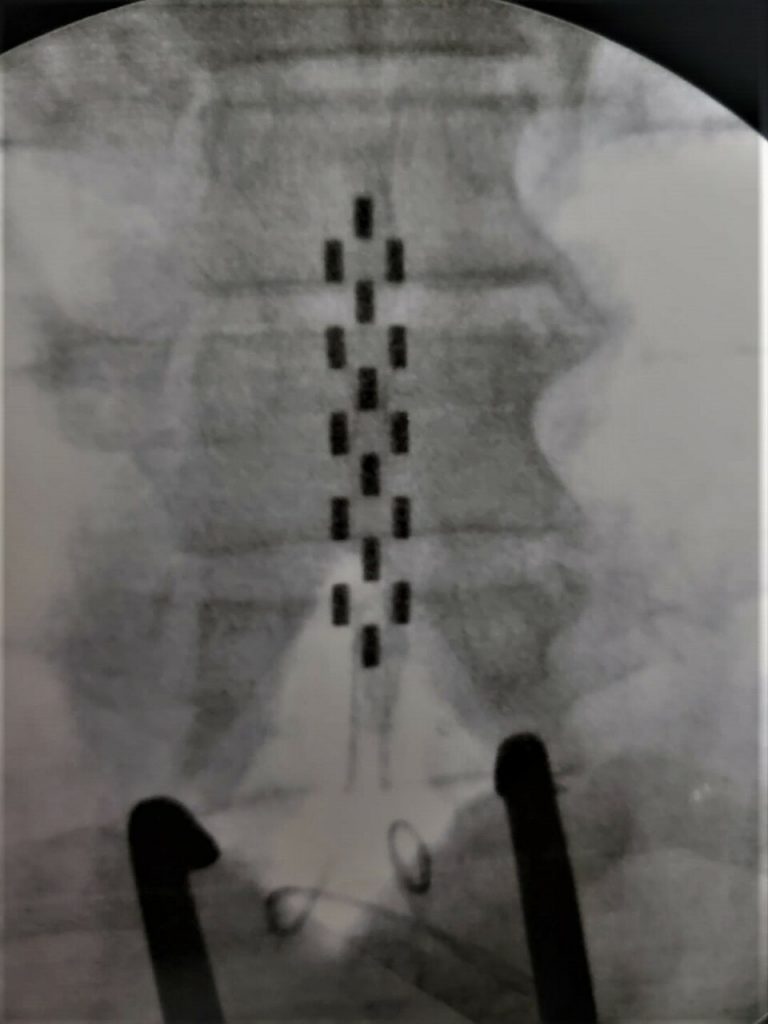

- Radiografia do pós-operatório de Implante de Neuroestimulador Medular (Eletrodo em Placa 32 contatos).